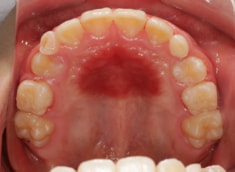

解説:上顎の急速拡大により、骨格的に拡大、前方牽引を促します。

上下顎の幅径と大臼歯の傾斜のギャップは平均値を越えて大きくなっており、上顎劣成長が顕著です。

上顎劣成長の場合、統計的に左上犬歯のスペースに注意する必要があります。